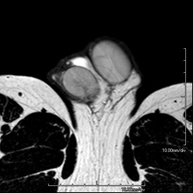

RM Escrotal (testicular)Prova diagnòstica no invasiva que consisteix en l'obtenció d'imatges d'alta definició anatòmica de la regió escrotal mitjançant l'ús d'un camp electromagnètic i ones de ràdio (amb un emissor i un receptor). No utilitza radiació ionitzant. De vegades s'ha d'emprar contrast paragmanètic (Gadolini) per completar l'estudi. S'utilitza per a l'estudi detallat dels testicles, per identificar possibles tumors i diverses patologies i per visualitzar alteracions de les estructures adjacents.